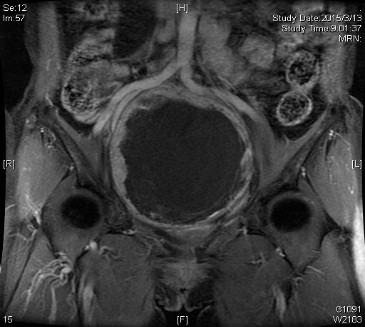

经进一步术前检查发现,尚女士肿瘤位于盆腔内,大小约25*20*20cm,瘤蒂位于右侧骶1-2骶前孔,部分实性成分位于右半骶骨内,在骶孔中塑形生长,手术暴露困难;瘤周异常血管网丰富,与髂总及髂内血管及骶前静脉丛毗邻,术中极易发生难以控制的大出血。不仅如此,肿瘤邻近膀胱、子宫及直肠,周围脏器易受损伤;右侧输尿管下段受到肿瘤压迫,右肾积水征象明显。为确保手术的安全性,术前神经外科、普外科、泌尿外科、血管外科等多名专家对病例进行了多学科讨论。血管外科吴巍巍主任指出,为预防术中发生大出血可考虑先予以腹主动脉球囊阻断,多次与患者及家属沟通,遗憾的是患者及家属拒绝预先行阻断手术,术中出血的风险再次增加。